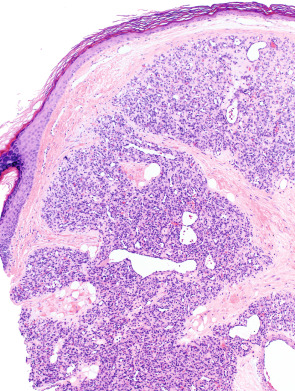

Tufted angiomas, as originally described in the dermatology literature, are characterized by multiple discrete lobules of capillaries set within the dermis and often the subcutis in a so-called “cannonball” pattern ( Fig. 114.14 ). Borders of the area of tissue involvement are poorly defined. The dermal collagen and subcutis separating capillary lobules may be histologically normal, but are often fibrotic. The lobules are composed of tiny capillaries with pinpoint lumina, occasionally containing fibrin microthrombi, that are tightly packed together without intervening stroma and frequently bulge into peripherally placed thin-walled vessels ( Fig. 114.14 , inset). Mitotic figures are rare.